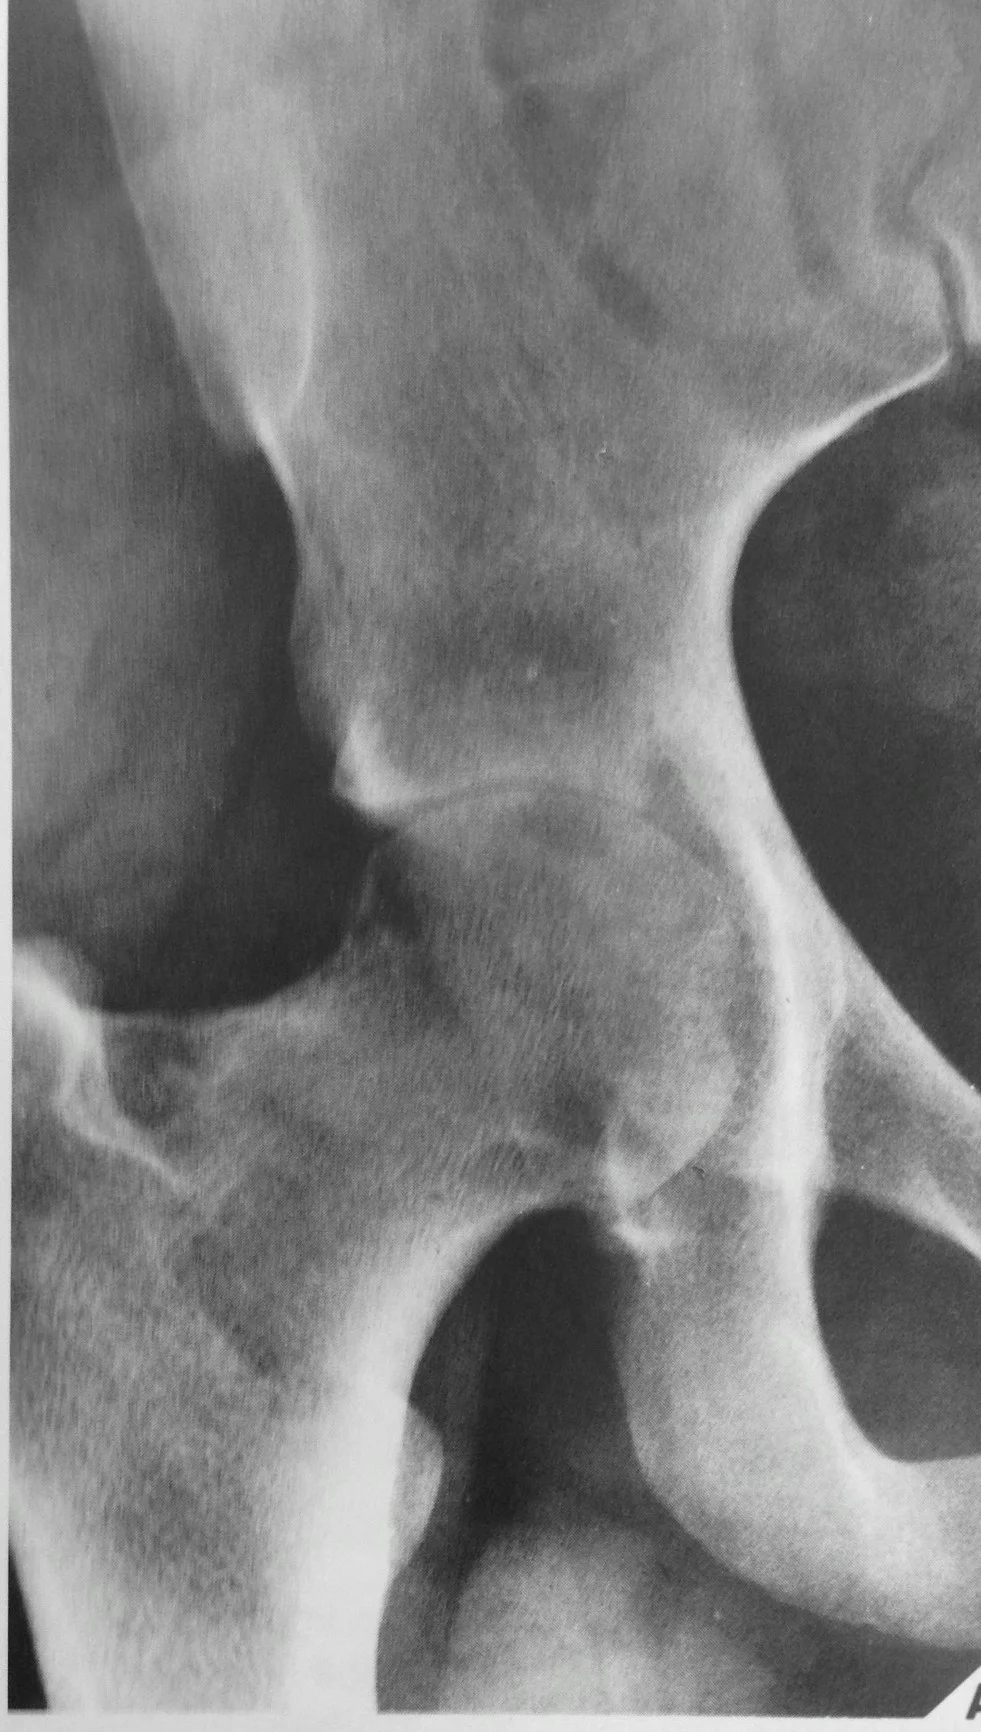

Plain X-rays

- Joints: usually monoarticular

- Peri-articular osteopenia

- Subchondral and peripheral erosions affecting both sides of the joint

- Loss of joint space